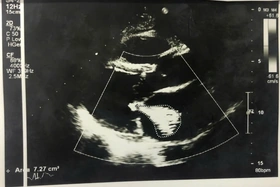

Người bệnh nữ (68 tuổi) ở Việt Trì, bị zona thần kinh vùng thành ngực và đau nhiều ở khu vực bị zona. Người bệnh đi khám thì phát hiện có khối bất thường kích thước lớn ở tim bên phải.